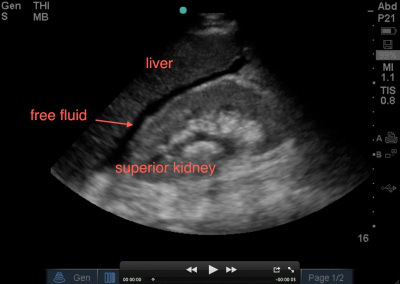

The RUQ is the most sensitive region for free fluid in comparison to the other eFAST views.

The RUQ should be divided into 3 zones.

1. Above/Below the diaphragm,

2. Morrison’s pouch (hepato-renal recess)

3. Para-colic gutter: Around the inferior hepatic edge/inferior pole of kidney

The key is to know your landmarks, and STOP, STAY and widely FAN through each zone well, adjusting your depth as necessary to keep the area of interest centered on your screen.

Start high to stay and fan (anterior to posterior) around the diaphragm. Then, SLIDE down into another rib space, stop, stay and fan around the entire kidney. An additional rib space may be necessary to evaluate the para-colic gutter.

Tips for RUQ Morrison’s Pouch (Hepato-Renal Recess) View:

If rib shadows get in the way, using the same trick above of patient inspiration can help. There are also a few false positive “traps” here.

First, the double line sign, seen around the kidney capsule as hyper-echoic double lines with hypo-echoic material in between, can be mistaken for free fluid. SEE ABSTRACT. However, free fluid will not be surrounded by hyperechoic lines and will not be in a contained structure.

Second, edge artifact from the liver/kidney interface occurs due to ultrasound physics and sound wave transmission between structures of different densities. It is seen as a dark thin line tracing off the edge of this interface extending to the bottom of the screen. . This differentiates it from free fluid, which will not extend past the liver.